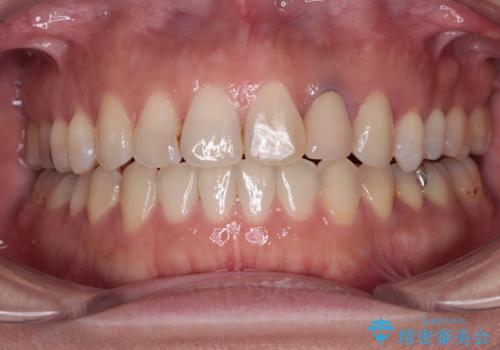

開咬と変色した前歯 インビザライン矯正とオールセラミッククラウン治療

- 前歯の開咬と失活により変色した前歯を気にして来院された患者様です。

矯正治療が概ね終了した時点で前歯をオールセラミッククラウンにて補綴治療を行い、その後インビザラインにて細かい部分を仕上げていくことしました。

オープンバイトは舌の突出癖により誘発され、治療後も突出癖が残っている容易に後戻りしてしまいます。

治療期間を短縮するためにも、舌突出癖の改善が極めて重要となります。